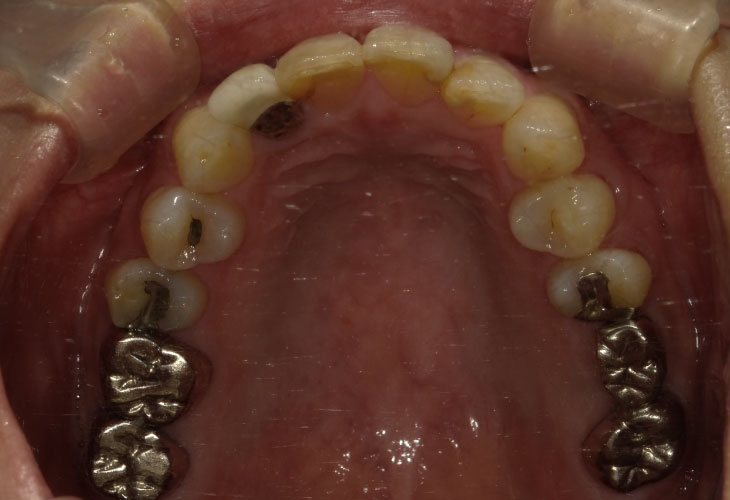

AFTER

インプラント(右下6・7)

オールセラミックス(左上2)

E-MAX CAD(左上6・7)